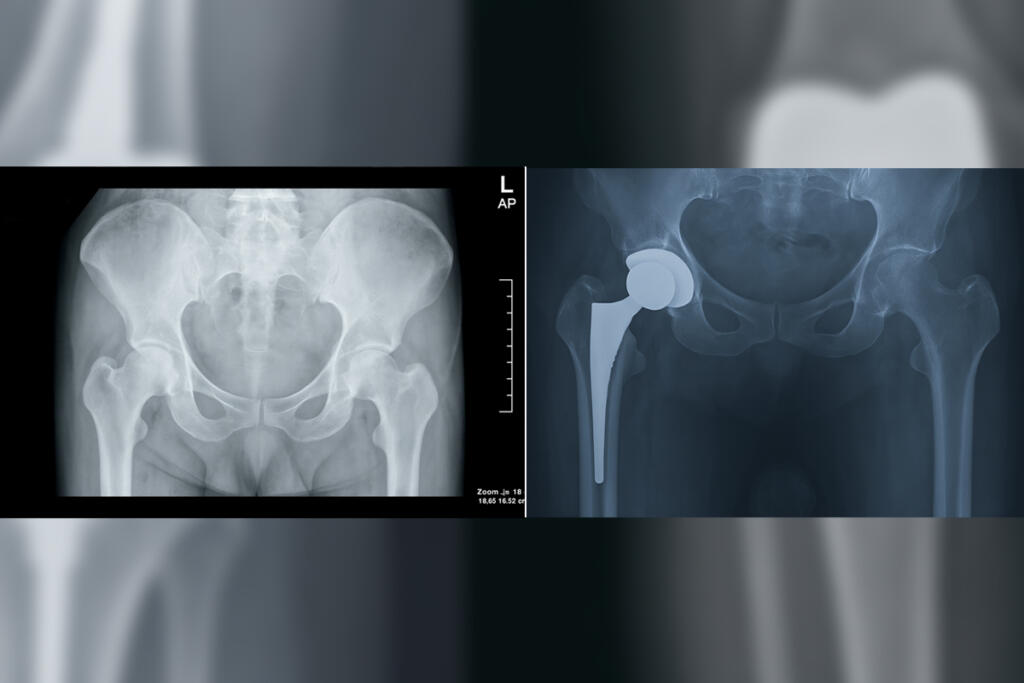

Primary Hip Replacement

Primary Hip Replacement is a surgical procedure that replaces a damaged hip joint with an artificial implant to relieve pain and improve mobility...

Revision Knee Replacement is a surgical procedure to replace a previously implanted artificial knee joint that has worn out or failed...